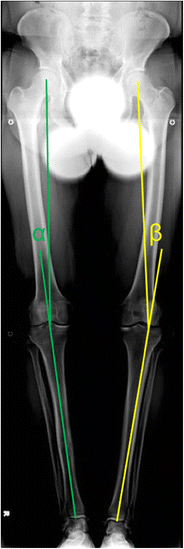

Purpose of review: The purposes of this review are to (1) describe the anatomic and biomechanical rationale for high tibial osteotomy (HTO) in the setting of posterior cruciate ligament (PCL) deficiency, (2) review the indications for concomitant HTO and PCL reconstruction, (3) provide guidance for the clinical assessment of the patient with suspected PCL deficiency, and (4) summarize the key surgical steps necessary to attain the appropriate sagittal and coronal plane corrections.

Recent findings: The preponderance of available biomechanical data pertaining to the PCL-deficient knee suggests that an increased proximal tibial slope limits posterior tibial translation under axial compressive loads. Moreover, recent clinical data has demonstrated that decreased proximal tibial slope may exacerbate residual anterior-posterior laxity and jeopardize the durability of PCL reconstruction. Thus, in the setting of PCL deficiency, an HTO that increases the posterior tibial slope may be advisable. HTO may be an important treatment adjunct in the surgical management of PCL deficiency. In the setting of chronic injuries and varus malalignment, HTO should be considered in order to ensure a durable ligamentous reconstruction and forestall the progression of secondary osteoarthritis.